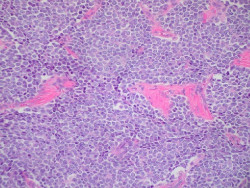

Desarrollan un nuevo tratamiento que funciona en tumores sólidos de alto riesgo con menor toxicidad

Investigadores del Children`s Hospital of Philadelphia (CHOP), en Estados Unidos, han desarrollado un tratamiento que ha mostrado éxito en tumores sólidos de alto riesgo que no sólo supera la resistencia común a los medicamentos sino que tiene el potencial de provocar menos toxicidades que la mayoría de los tratamientos contra el cáncer, según publican en `Cancer Research`, la revista de la Asociación Estadounidense para la Investigación del Cáncer.